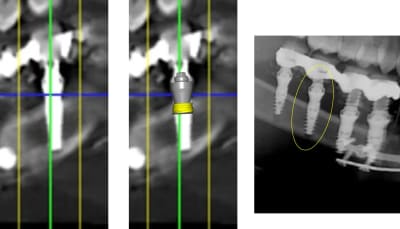

1 se baser sur la pano pour en tirer des conclusions est une erreur de débutant

2 sur les coupes scanner une partie du col est infra osseuse et l'autre non

> 1 se baser sur la pano pour en tirer des conclusions est une erreur de débutant

>

> 2 sur les coupes scanner une partie du col est infra osseuse et l'autre non

mais posit... y'a que toi qui pense que l'implant est aussi enfoui... ca saute aux yeux que tu fais tout pour grater 1mm d'enfouissement... pour qu'ils paraissent pas si mal posé que ca...

avec, par exemple, ton implant de 10mm qui est contenu dans 9mm... t'es le Gérard Majax des guides chir.

comme ici... si e carré fait 4,5 alors l’implant ne fait pas 10 mais moins de 9...

Tout comme l’autre implant pas 11,5 mais 10,3

heureusement que ta méthode est "précise" ;)

En traçant le col de l'implant comme tu le fais tu ne tiens pas compte que le pilier fait 4,5 mm de hauteur, normalement tu devrais arriver à le comprendre tout seul !